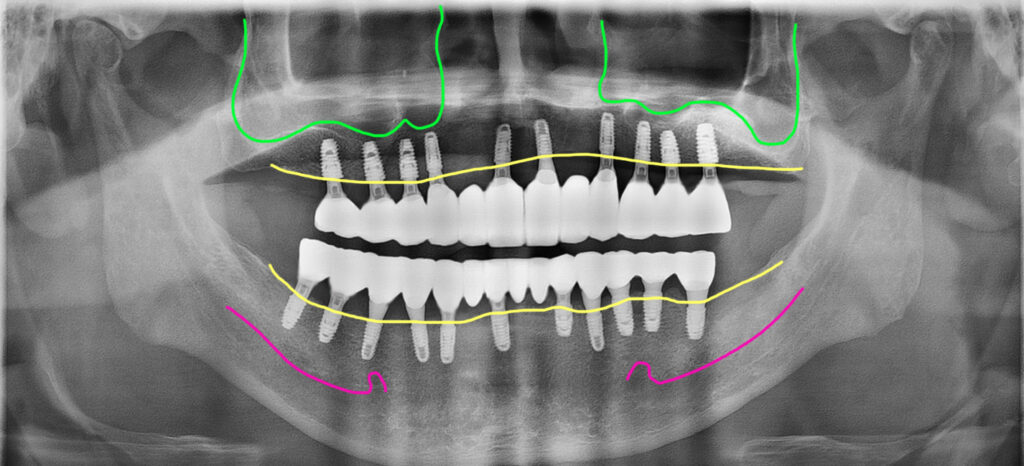

최종완성 위아래 전체임플란트를 크라운 브릿지 방식으로 완성

이 분은 위아래 충분한 개수의 임플란트를 식립해서 자연치와 가장 유사한 형태의 보철인 크라운 브릿지 방식으로 치료를 마무리한 모습입니다.

현재 이 분은 6년째 별다른 문제없이 잘 사용하고 계시고 정기검진도 잘 받고 계세요.